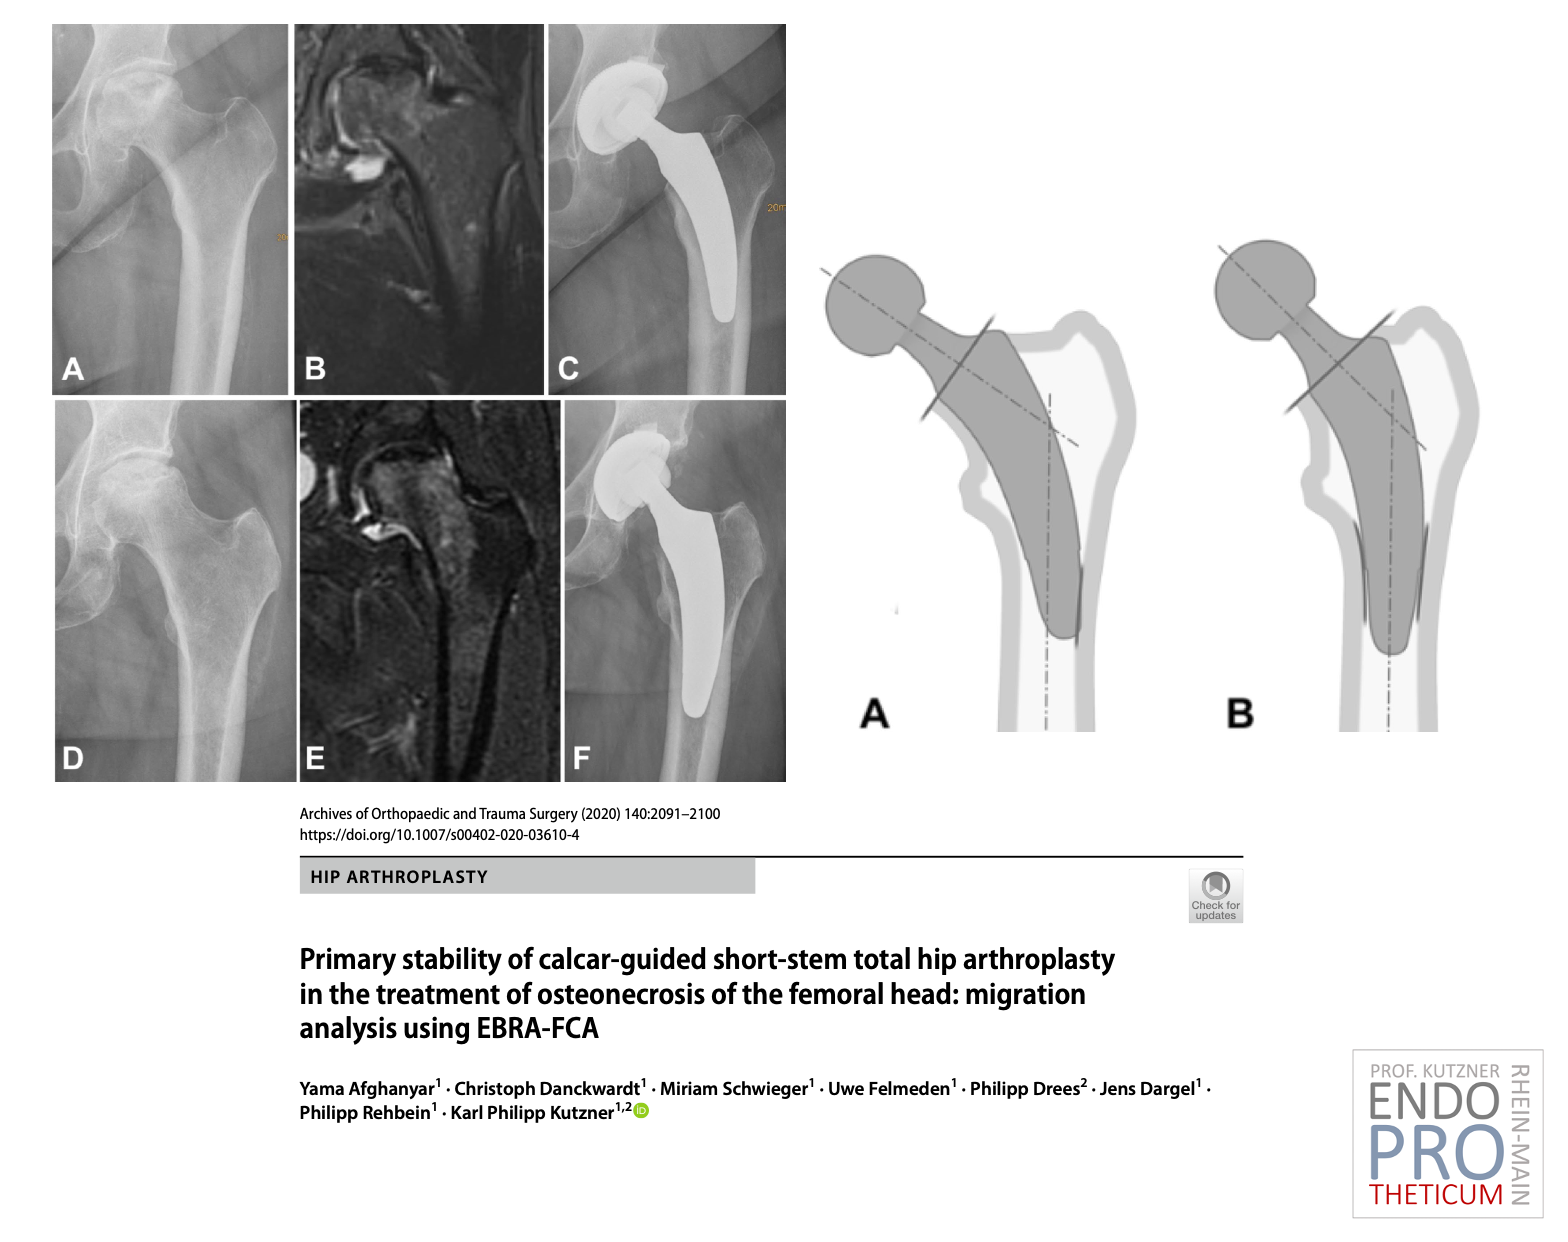

Le concept de tiges courtes modernes guidées par le calcar dans l'arthroplastie de la hanche vise à la reconstruction précise de la géométrie anatomique individuelle de la hanche. Une technique d'implantation douce pour les os et les tissus mous est utilisée en association avec une mise en charge physiologique dans la partie du fémur proche de l'articulation afin de préserver l'os à long terme.

Les tiges courtes et rondes s'adaptent parfaitement à l'ALMIS ACCESS peu invasif ; aucun dommage musculaire n'est nécessaire. Contrairement aux tiges droites conventionnelles, l’implantation est réalisée à l’aide de la technique du « tour du coin ».